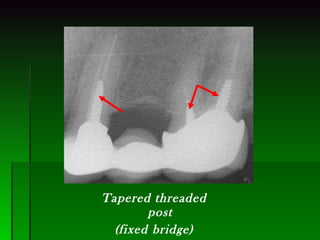

Tapered threaded post (fixed bridge)

Tapered threaded post(fixed bridge)